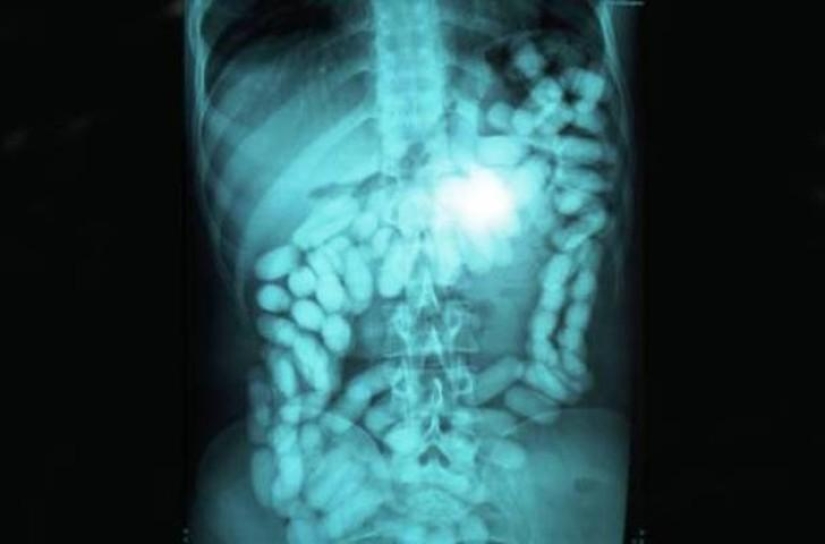

Enorme ovillo de lana.